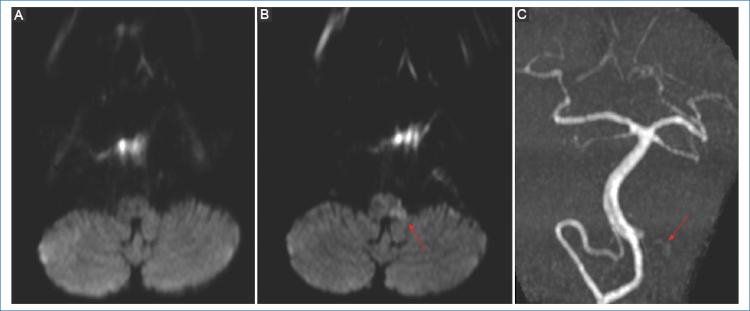

No obstante, a pesar de la alta sensibilidad de las secuencias de DWI, está descrito en la bibliografía que pequeñas lesiones ubicadas en el tronco encefálico con sintomatología leve (como la oftalmoplejía internuclear) pueden ser invisibles inicialmente5,7 (Fig. 3).

El foramen oval permeable (FOP) usualmente produce pequeñas lesiones corticales, únicas o múltiples, en la circulación vertebro-basilar, así como en el tálamo12 (Fig. 5).